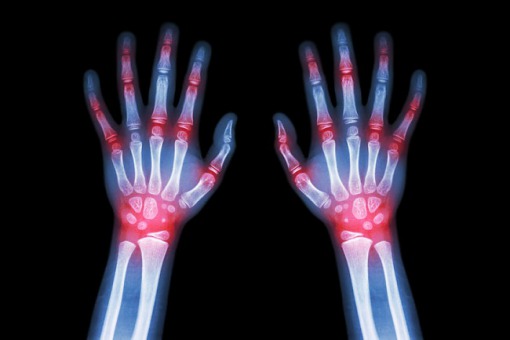

Najczęstszą pozajelitową manifestacją nieswoistych zapaleń jelit (ang. inflammatory bowel diseases, IBD) jest seronegatywne zapalenie stawów. Jednakże, pacjenci z IBD mogą również chorować na reumatoidalne zapalenie stawów (ang. rheumatod arthritis, RA), które występuje częściej w populacji ogólnej niż zapalenia seronegatywne.

Na łamach BMC Gastroenterology opublikowano przegląd systematyczny z meta-analizą oceniający częstość występowania RA u pacjentów z IBD. Badacze zidentyfikowali 3 badania kohortowe, 3 badania przekrojowe oraz 2 badania typu case-control studies. W porównaniu do osób nie chorujących na IBD, pacjenci z IBD mieli znacznie zwiększone ryzyko zachorowania na RA (RR=2,59; 95% CI: 1,93 - 3,48). Ryzyko było większe w przypadku pacjentów z chorobą Leśniowskiego-Crohna (RR=3,14; 95%: CI 2,46 – 4,01) niż w przypadku pacjentów z wrzodziejącym zapaleniem jelita grubego (RR=2,29; 95% CI: 1,76 - 2,97).

Pacjenci z IBD mają nie tylko zwiększone ryzyko seronegatywnych zapaleń stawów, ale również RA. Stąd, należy zachować szczególną czujność w różnicowaniu etiologii zapalenia stawów występującego u tych pacjentów.